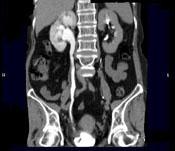

问题 女,64岁,反复尿频尿急尿痛6年余,尿常规检查:红细胞(++),白细胞(++)CT扫描如图示,下列说法正确的是 ( )

选项 A、考虑为慢性输尿管炎 B、考虑为输尿管移行细胞癌 C、右肾积水 D、右侧输尿管上段扩张 E、右侧输尿管下段管壁增厚,管腔狭窄

答案 ACDE